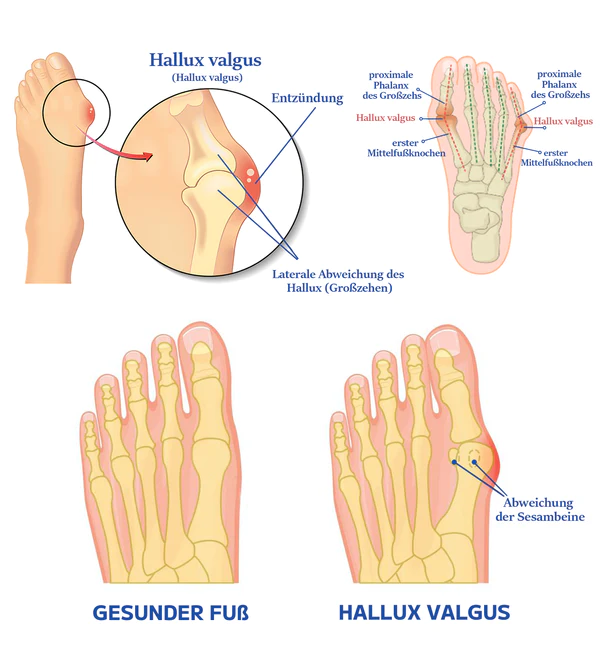

Was ist ein Ballenzeh?

Ein knöcherner Knubbel, bekannt als Hallux valgus, bildet sich an der Basis des Großzehengelenks. Dies geschieht, wenn einige der Knochen im Vorderfuß aus der Ausrichtung rutschen. Das Gelenk an der Basis des großen Zehs wird gezwungen, hervorzustehen, weil die Spitze des großen Zehs zu den kleineren Zehen gezogen wird. Über dem Hallux valgus kann es zu Schmerzen und Entzündungen kommen.

Hallux valgus oder Ballen betreffen etwa 30% der Bevölkerung. Sie entstehen durch die Fehlstellung von Metatarsal- und Phalanxknochen im Fuß, was zu einer Entzündung und Vorwölbung des Gelenks führt. Genetik, Fußverletzungen, die die Knochenstruktur verändern, und schlecht sitzende Schuhe tragen zur Bildung von Ballen bei. Diejenigen mit einer erblichen Veranlagung, flachen Bögen oder einer Vorgeschichte von Fußverletzungen sind anfälliger. Enge oder hochhackige Schuhe erhöhen das Risiko. Ballen können unbehandelt im Laufe der Zeit schlimmer werden und Unannehmlichkeiten und Schmerzen verursachen.